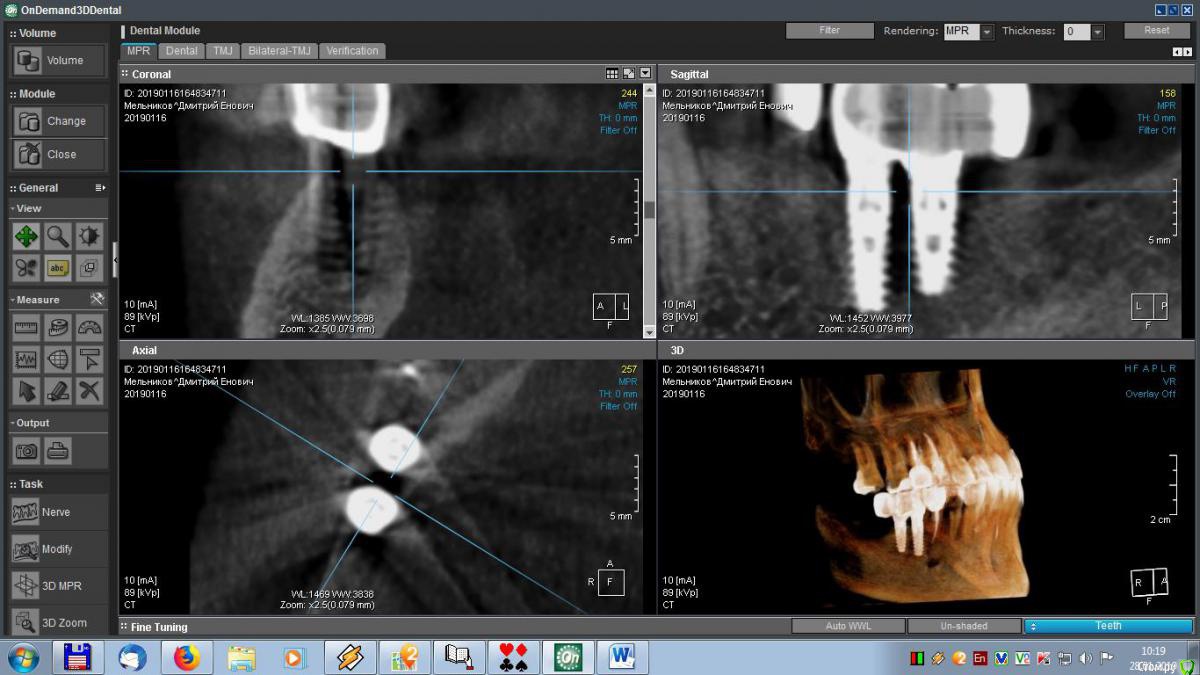

meld Опубликовано 29 января, 2019 Автор Поделиться Опубликовано 29 января, 2019 Здравствуйте, уважаемые доктора! Скоро год, как мне поставили метало-керамические коронки. До сих пор я ощущаю зуд в области имплантатов. На контрольном приеме врач ничего криминального не увидел, прописал чистку, фотосан и КТ, Я все сделал, по КТ врач сказал, что все нормально. Посмотрите, пожалуйста, мои среза и подтвердите (или нет) - все ли нормально. Спасибо. Ссылка на комментарий

meld Опубликовано 29 января, 2019 Автор Поделиться Опубликовано 29 января, 2019 Выложил больше срезов. Спасибо. Ссылка на комментарий

Борис80 Опубликовано 29 января, 2019 Поделиться Опубликовано 29 января, 2019 Все нормально, если не скапливается постоянно пища под дальним краем 7го зуба Ссылка на комментарий

Bier Опубликовано 30 января, 2019 Поделиться Опубликовано 30 января, 2019 на мой взгляд тоже все ок. Ссылка на комментарий